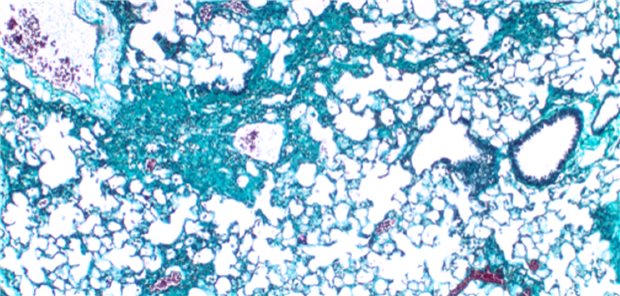

Forschende haben eine bisher unbekannte Ursache für die Entstehung der Lungenfibrose entdeckt. Ein darauf basierender neuer Therapieansatz sei vielversprechend.